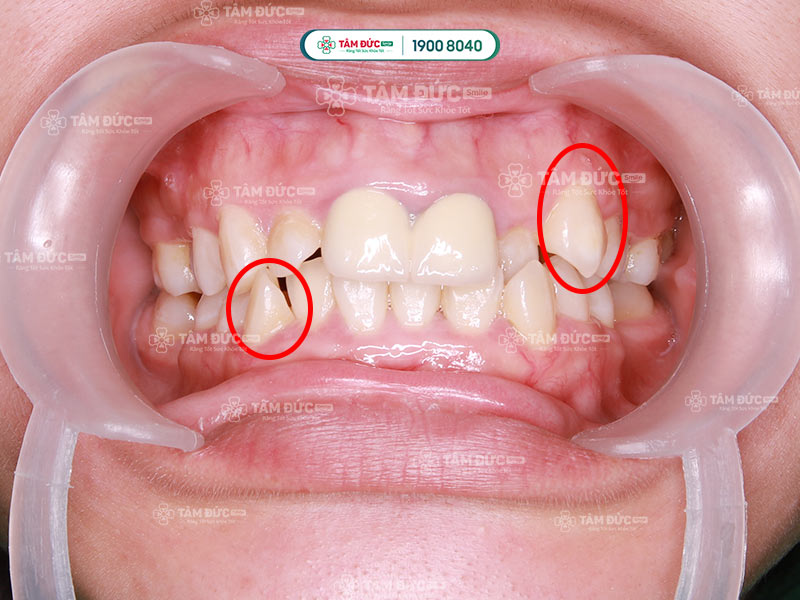

Răng nanh mọc lệch là khi răng nanh không nằm đúng vị trí và mọc không đều so với các răng còn lại. Điều này có thể làm thay đổi hình dáng tổng thể của hàm răng, làm ảnh hưởng thẩm mỹ nụ cười và làm giảm chức năng nhai.

Răng nanh mọc lệch có thể làm sai khớp cắn, cản trở việc vệ sinh răng miệng và tạo ra áp lực không đều trên các răng khác. Răng nanh mọc lệch có thể xuất hiện dưới nhiều dạng khác nhau, dưới đây là một số kiểu phổ biến:

Răng nanh mọc lệch